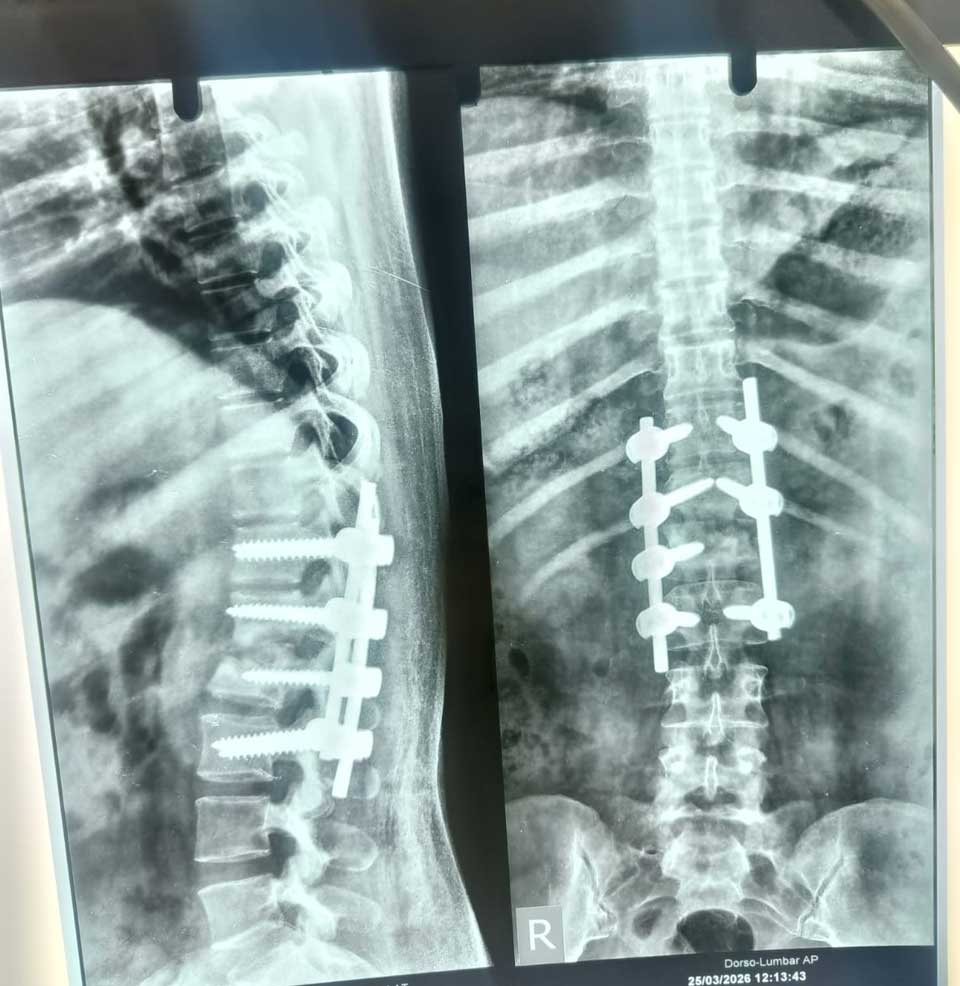

Our Image Gallery